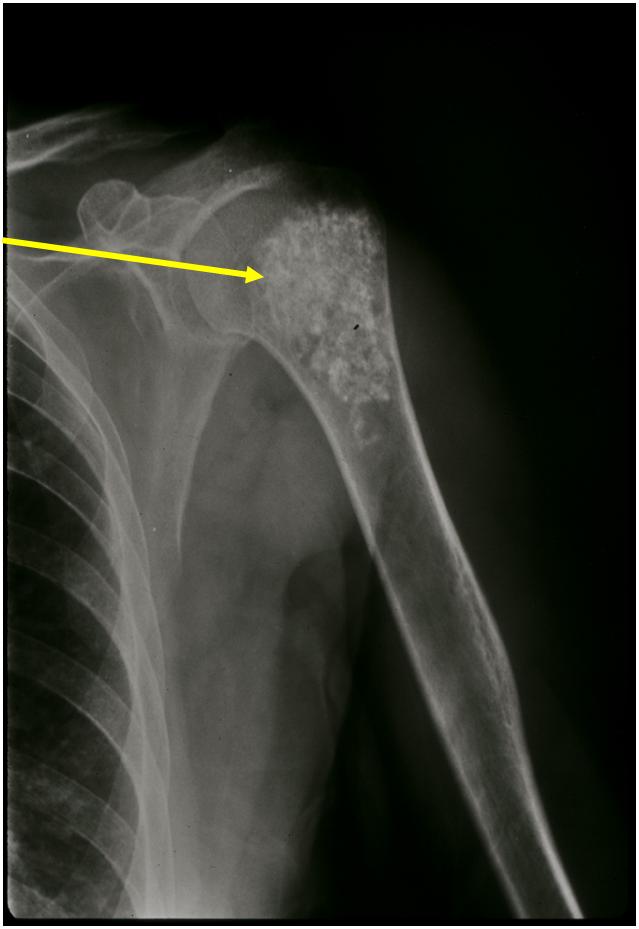

Рентгеновские снимки саркомы плечевого сустава